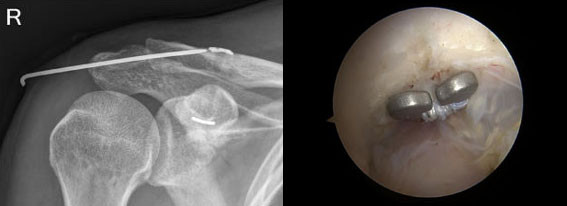

Á¤Çü¿Ü°ú ¼ö¼ú °ü·Ã SCI ±Þ ±¹Á¦ÇмúÁöÀÎ ±¹Á¦ÇмúÁöÀÎ ¡®Knee Surgery, Sports Traumatology, Arthroscopy¿¡ °ÔÀçµÈ Coracoid clavicular tunnel angle is related with loss of reduction in a single?tunnel coracoclavicular fxation using a dog bone button in acute acromioclavicular joint dislocation¡¯ ³í¹°Àº ¾î±úÀÇ °ß¼â °üÀý ¼Õ»ó¿¡¼ ³»½Ã°æ ¼ö¼ú ±â¹ýÀ» º¸°íÇÑ ¿¬±¸·Î ±âÁ¸ÀÇ ¼ö¼ú¹ýÀÇ ÀüÀ§ ¹ß»ýÀÇ ÇѰ踦 ±Øº¹ÇÏ¿© ¼ö¼ú ÈÄ ¿ì¼öÇÑ È¸º¹À» º¸°íÇÑ ³í¹®ÀÌ´Ù.

| | ¡è¡è ¡ã³»½Ã°æÀ» ÀÌ¿ëÇÑ °ß¼â °üÀý °íÁ¤¼ú ÈÄ ¹æ»ç¼±<¿ÞÂÊ>°ú ³»½Ã°æ<¿À¸¥ÂÊ> ¼Ò°ß <»çÁøÁ¦°ø=¾Æ»êÃæ¹«º´¿ø> | ¨Ï ¿Â¾ç½Å¹® | |